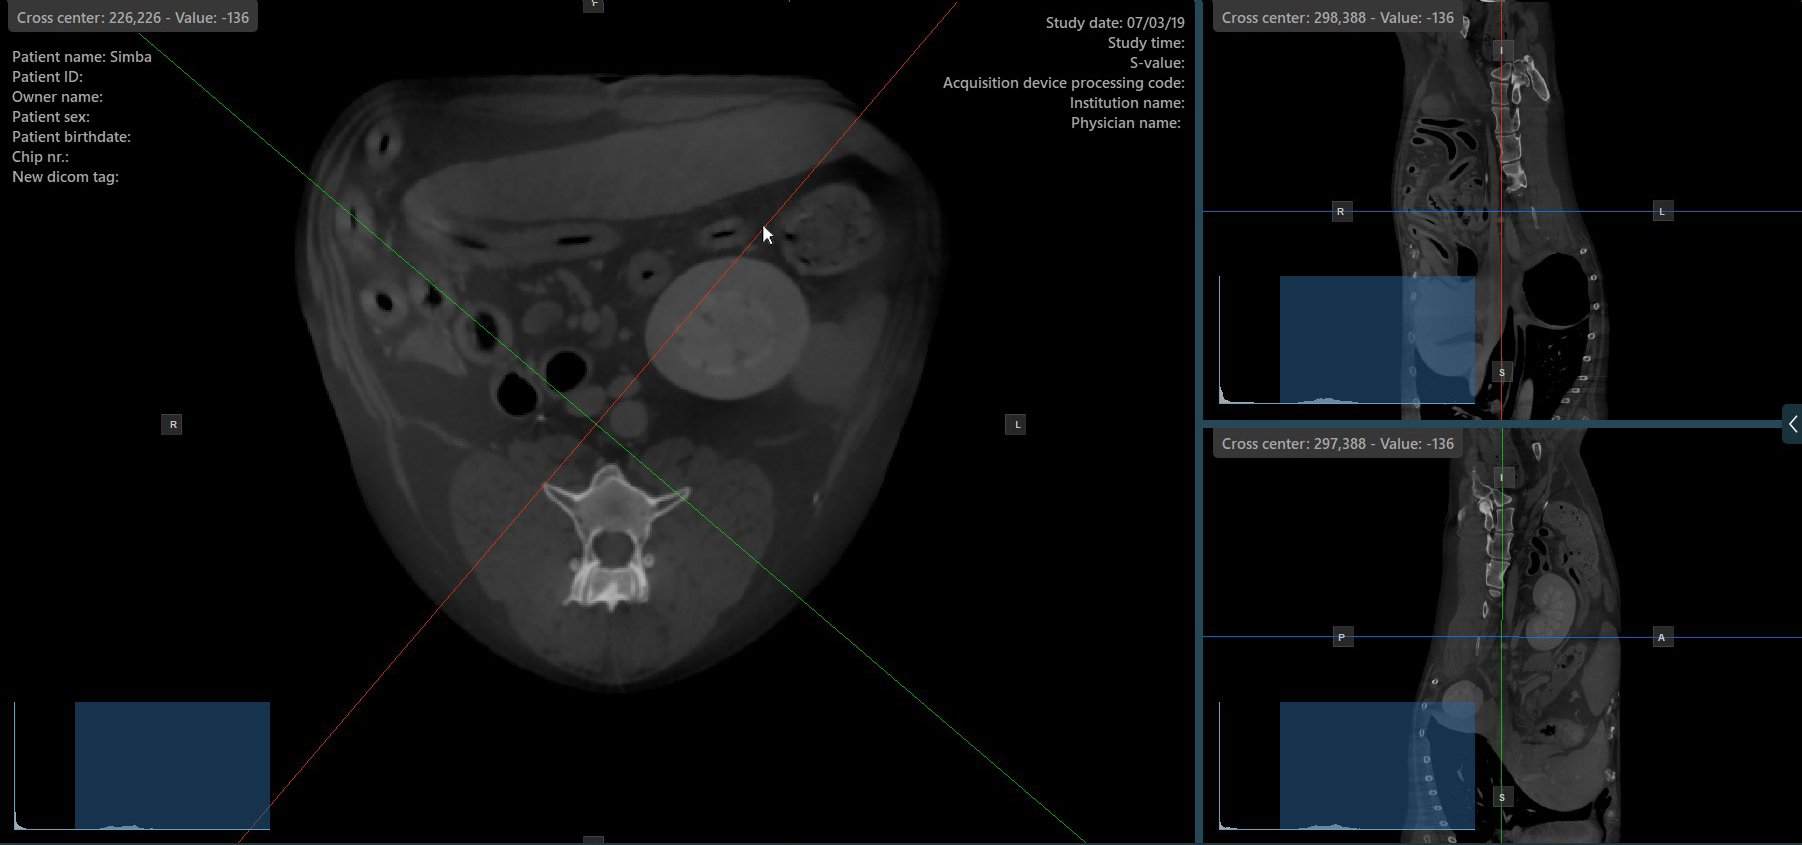

Change Slicers Cross Center Position¶

Altering the position of the cross center of slicers will change the position of the corresponding two image planes. The cross center of the slicers can be selected by using the Select Item (Default) tool, assigned to the right mouse

button by default.

Once selected, drag the cross center of the specific slicers to the desired direction to move its position. The corresponding image planes’ orientation changes accordingly.